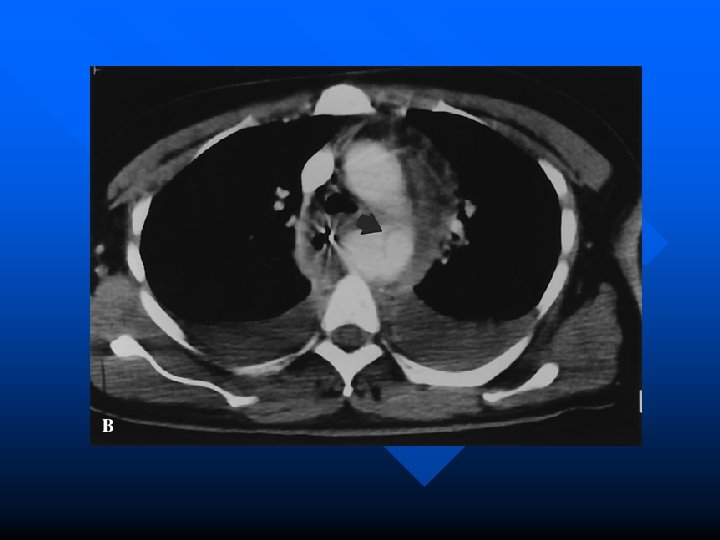

Radiography in TAI n Specific findings: – mediastinal widening – depression of left mainstem bronchus – loss of paravertebral stripe – NG deviation – lateral displacement of trachea – left apical cap – obscured aortic knob – widened paratracheal strip Difficult to assess mediastinal widening in pediatrics because of thymus

Radiographic Findings Table 3. Radiographic Findings of Mediastinal Hematoma Finding Sensitivity Specificity Mediastinal widening 50 -90% 10% Depression of the left mainstem bronchus 70 -80% 80 -100% Deviation of nasogastric tube 23 -71% 90 -94% 12 -100% 80 -95% 20 -63% 75 -76% Lateral displacement of trachea Left apical pleural cap Loss of paravertebral pleural stripe Obscured aortic knob Widened paratracheal stripe

CXR in TAI Despite multiple suggestive findings on CXR not completely reliable n The CXR visualises the mediastinum not the aorta n Sensitivity of widened mediastinum only 89% and of any abnormality 92 -98% n Take home message CXR will miss 2 -11% of injuries n

Aortography n n n The “gold standard” with sensitivity of 100% Also localizes the area of injury and can identify lesions in other vessels BUT – – n time consuming in location away from ED not readily available high contrast load Complication rate of 2. 6 % in series of trauma patients Reid et al. The assessment of proximity of a wound to major vascular structures as an indication for arteriography. Arch Surgery 1988; 123: 942 -946.

Chest CT n Many advantages over aortography – readily accessible in most urban ED’s – low complication rate – less contrast – fast – gives information about structures other than the aorta

Evidence for CT in Blunt Trauma? n Early scanners (non-helical) were disappointing but new helical CT’s have sensitivities of 100% and specificity of 96 % Mirvis et al. Traumatic aortic injury. Diagnosis with contrast enhanced thoracic CT—five year experience at a major trauma center. Radiology 1990; 176: 181 -183 Garrant et al. Blunt traumatic aortic rupture. Detection with helical CT of the chest. Radiology 1995; 197: 125 -133. n Demetriades et al. concluded that “all trauma patients with high risk deceleration injuries undergo routine helical CT irrespective of CXR findings” Demetriades et al. Routine helical CT evaluation of the mediastinum in the high risk trauma patient. Arch Surg 1998; 133: 1084 -1088.